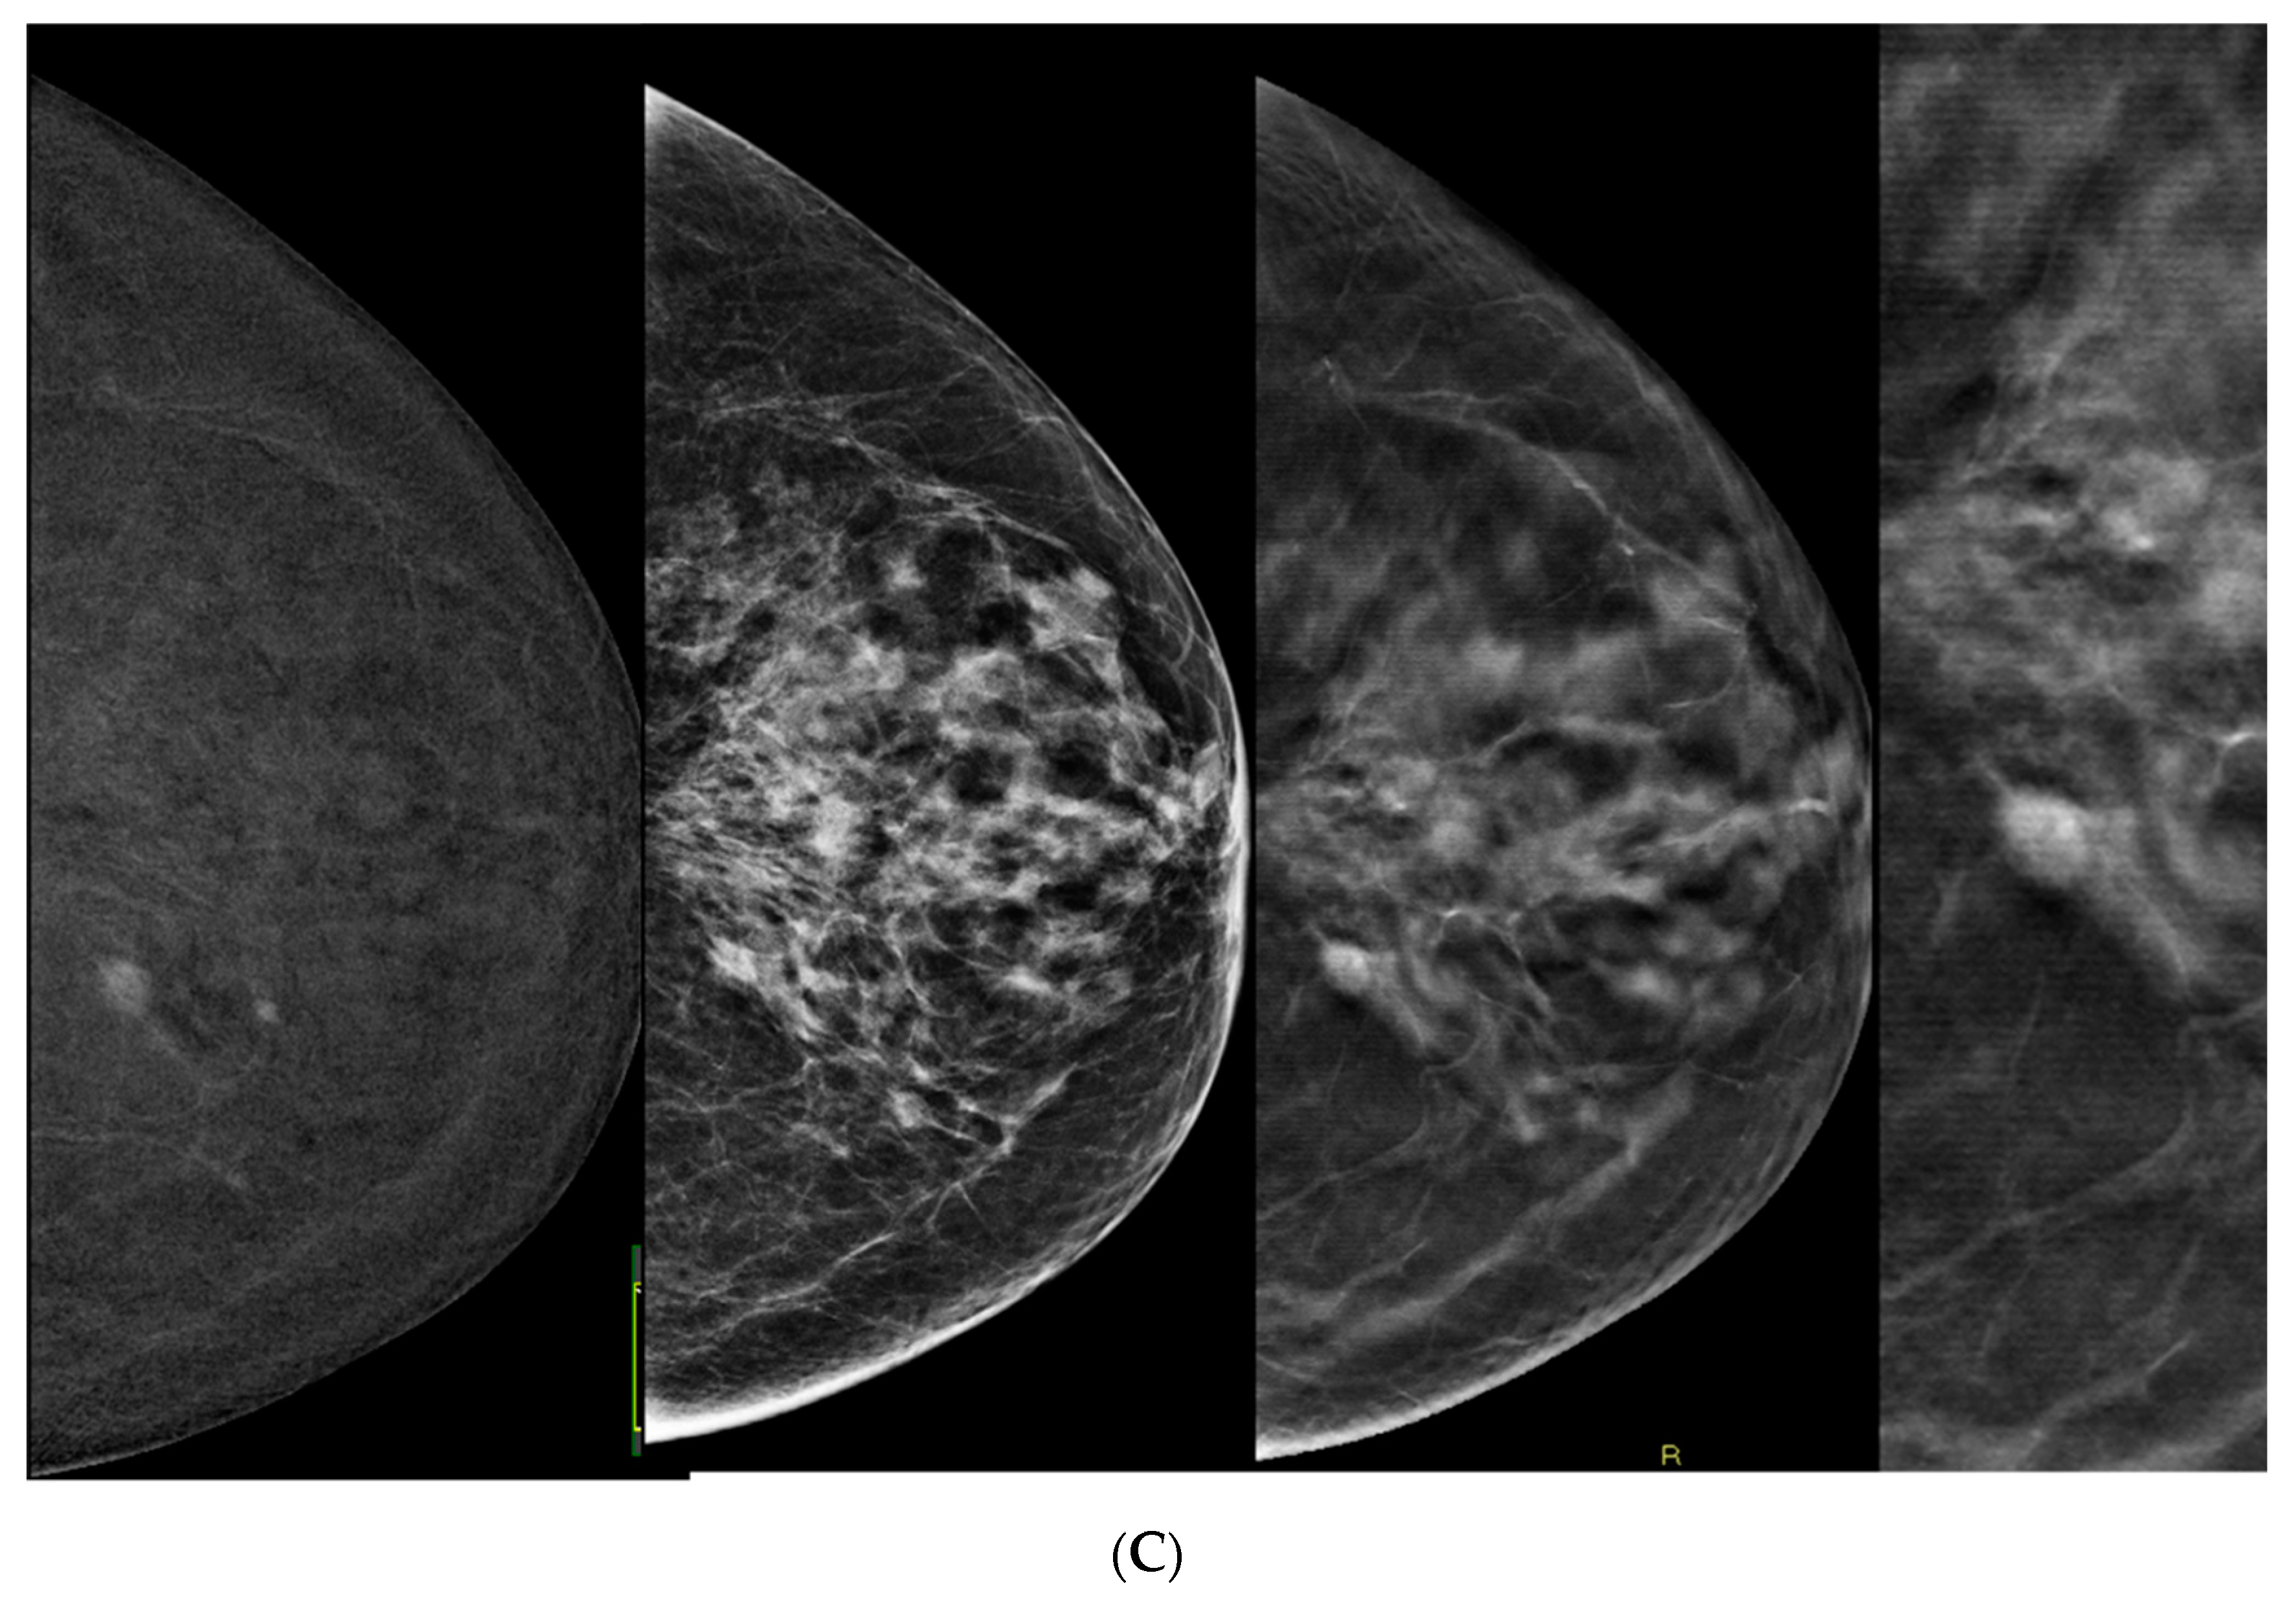

- Incorporating DBT into CEM-detected lesions leads to a significant upgrade in BIRADS scores toward the lesion’s true pathology (p > 0.0001).

- This was consistent across all readers, with particularly notable differences observed among less experienced readers.

- The primary driver for the score upgrade was attributed to improved margin visibility facilitated by DBT.